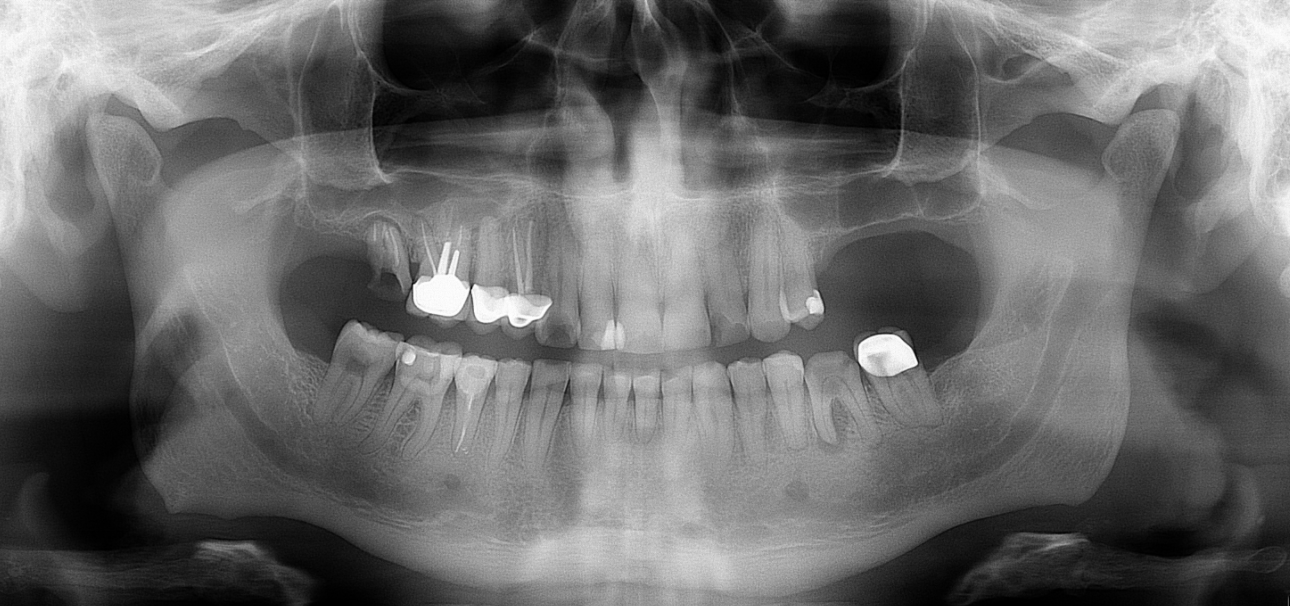

Klinikai és radiológiai vizsgálatok alapján megállapítottam, hogy a túlterhelés (parafunkciók) jelei látszódnak a fogain is: abfrakciók – nyaki kopások és attríciók –, rágófelszíni kopások is kifejezettek voltak. Harapása igen bizonytalan tartományban mozgott, nem volt egy stabil helyzet, amelybe határozottan össze tudott volna zárni (csak kereste a megfelelő pozíciót.) TMI-vizsgálat során reciprok crepitációt (kattanás nyitáskor-záráskor is), myofascialis eltéréseket (hypertrófiás musculus masseter – túlterhelt rágóizom) és beszűkült mozgáspályákat találtam. Emellett sajnos a nem megfelelő szájhigiénés szokások miatt a fognyakak „sérült” részein szuvasodások is megjelentek, illetve a bal alsó hatos és a jobb felső hetes fog már oly mértékben destruálódott, hogy el kellett távolítani őket.